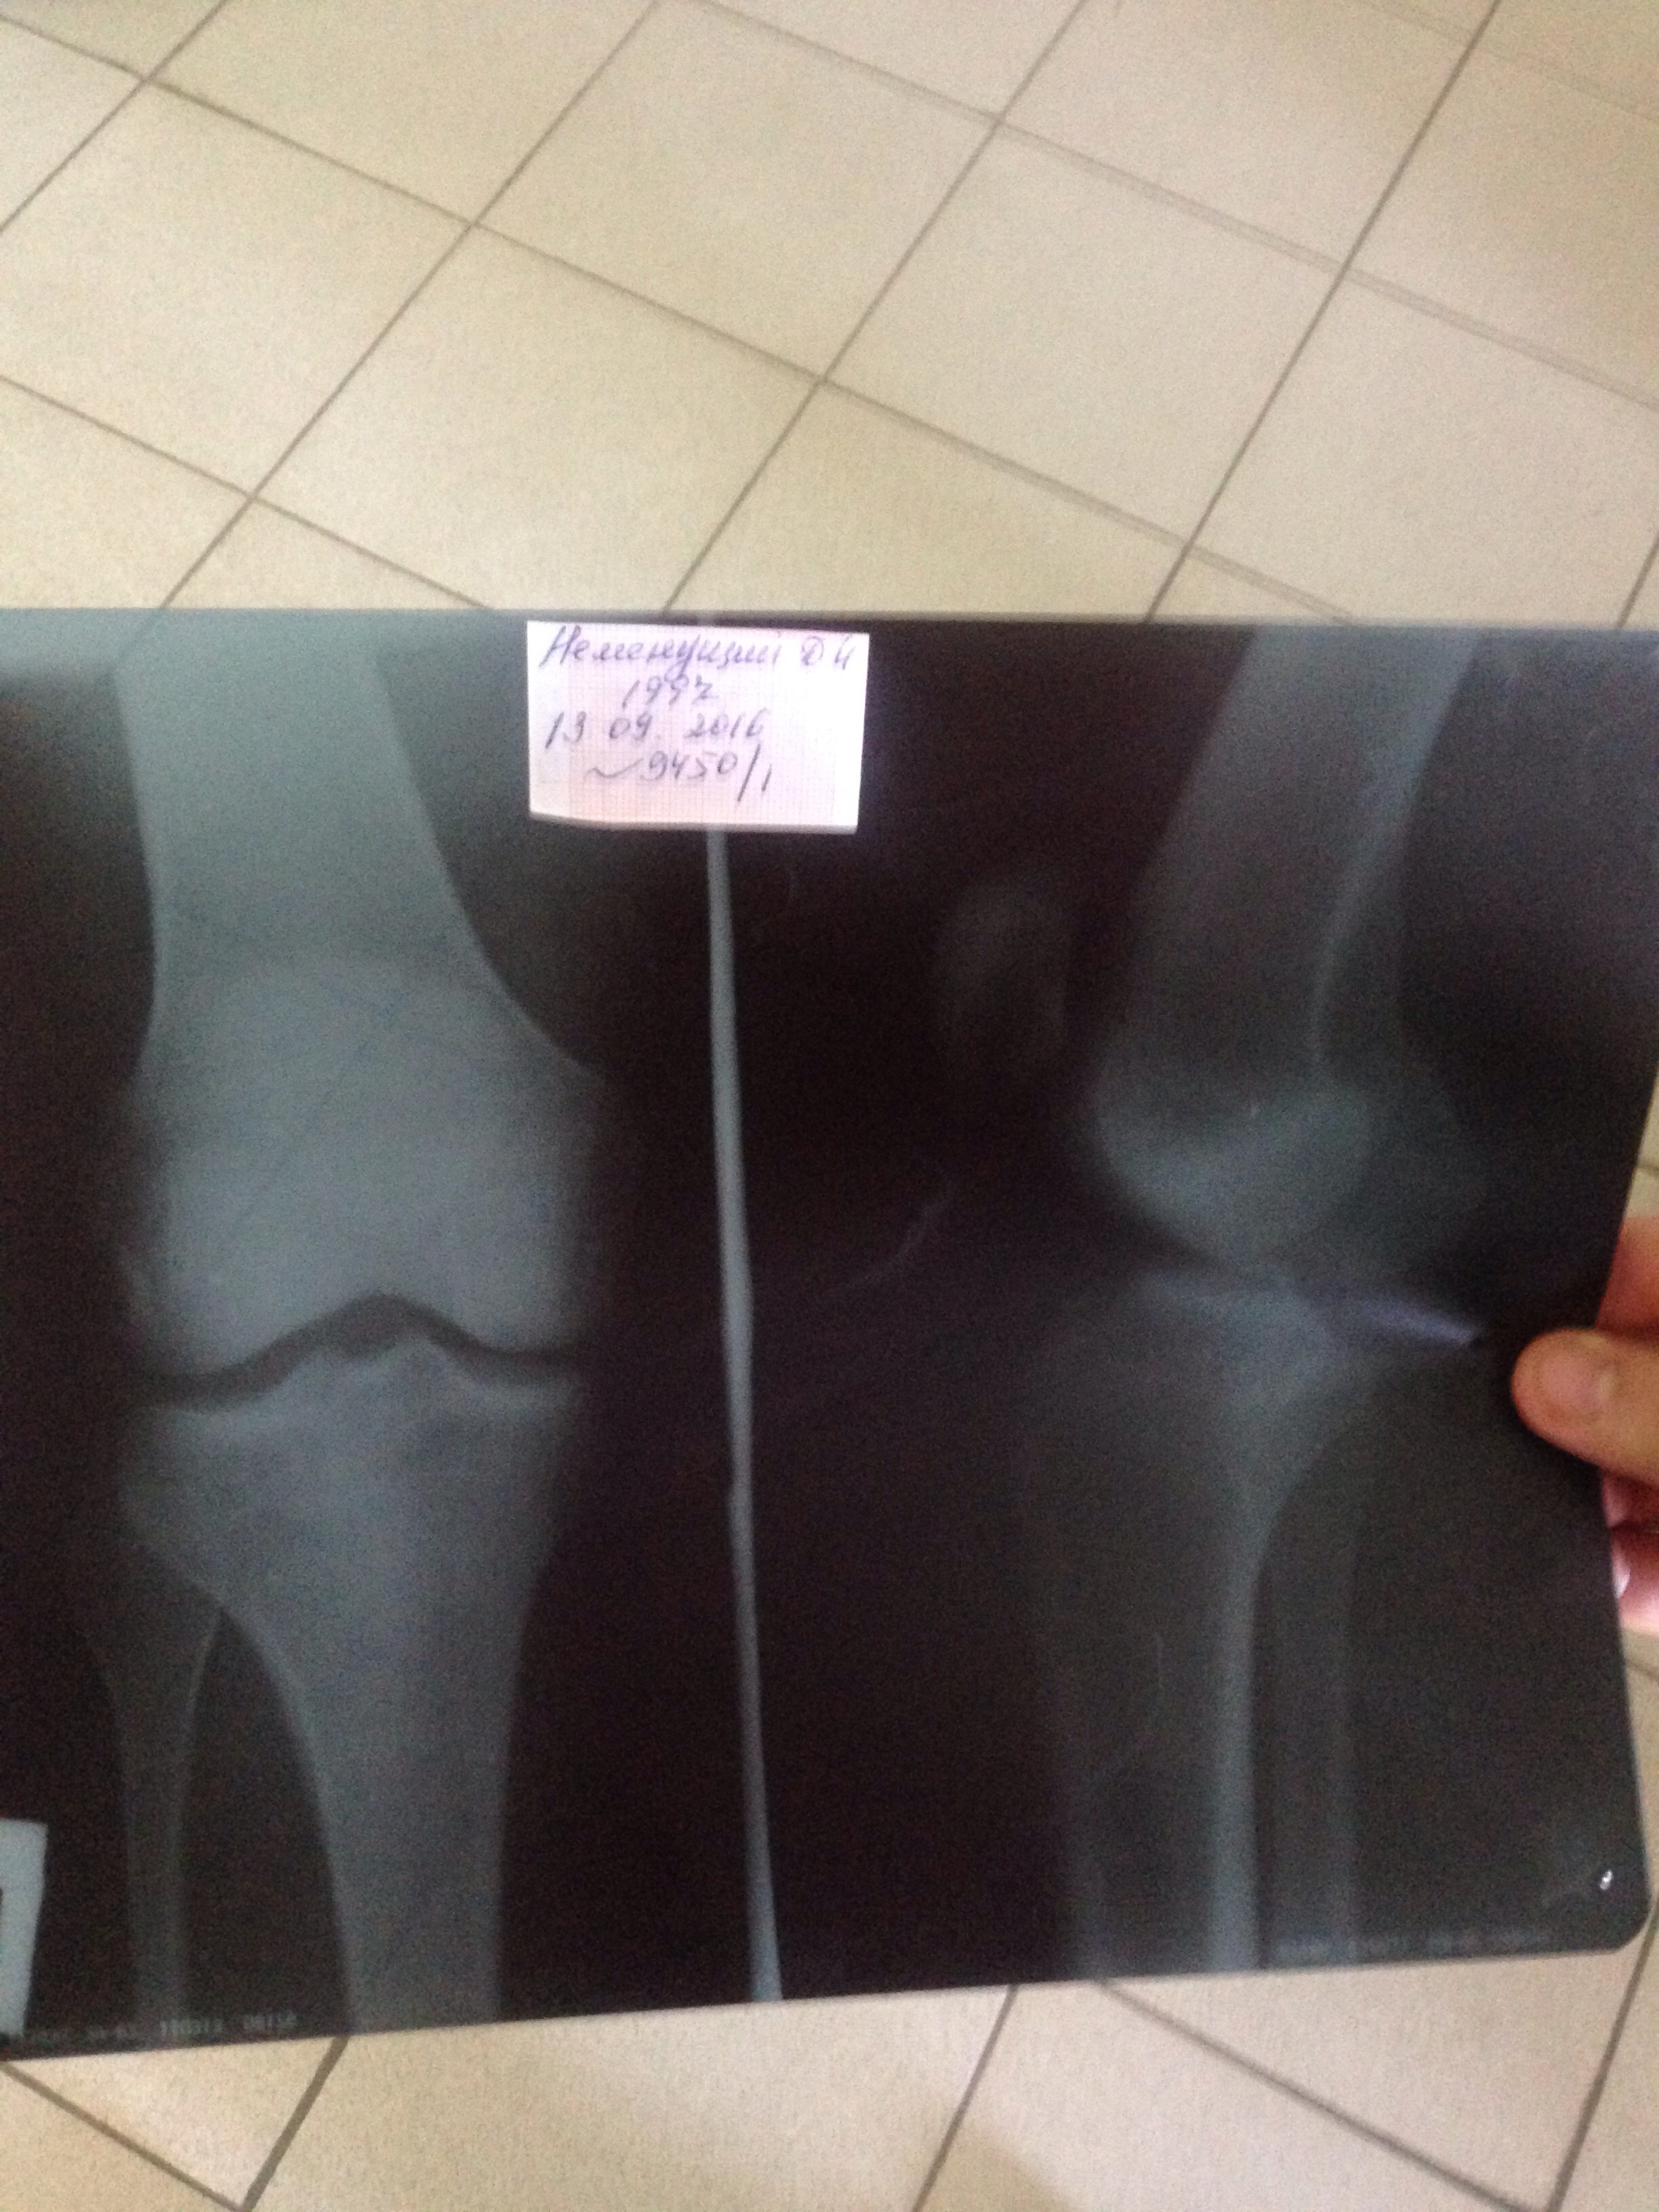

На ренгене ничего и не увидишь. Надо было мрт делать. А на процедуры ходи, когда плечо болело, помогло.

Снимок делал? Что за диагноз поставили?

Никогда не назначаю УВТ при воспалении собственной связки надколенника (не люблю слово тенденит касательно связок). Смысл долбить в связку, если причина её воспаление в укороченном и гипертоничном квадре либо в проблеме с ТБС или голеностопным, которая всплывает в коленном.

При воспалении собственной связки надколенника хорошо помогает МФР четырехглавой и ягодичных и стретчинг. Укреплять мышцу нужно сначала только в эксцентрическом режиме, что позволит растянуть соединительно-тканные элементы мышцы. Приседания на одной ноге и только в эксцентрической фазе, в положении дорсифлексии стопы отлично помогут.